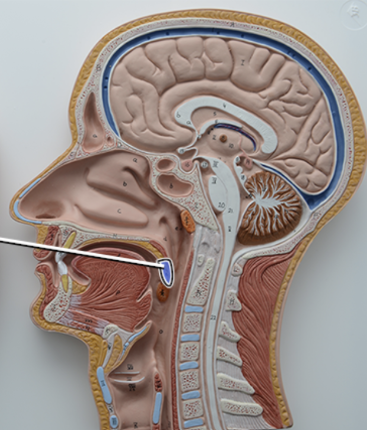

What structure is this?

Uvula